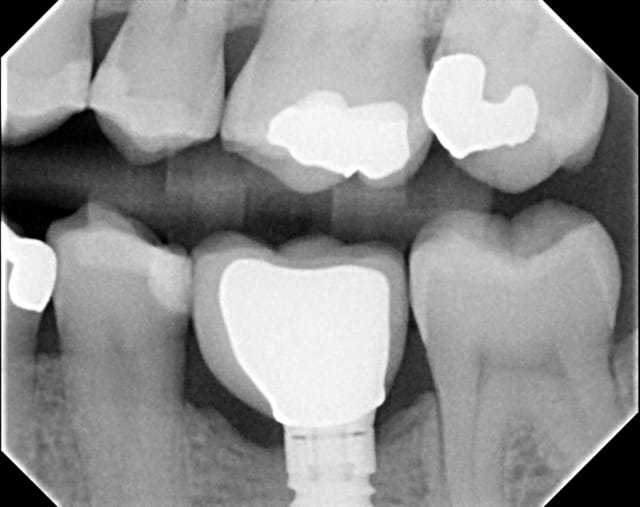

Contrôle post-op 2 ans.... reformation osseuse....

les 2 dernières radiographie sont inversées pour l'ordre chronologique

Novembre 2012 s3atpd - Eugenol

Pour les radio... excuse pxav... il s'agit de BW (interproximal) seul l'angulation mésio-distal change...on voit quand même un trait noirâtre entre l'os présent ert la néoformation....bravo patient mais arrête sinon la couronne va se décimenté...